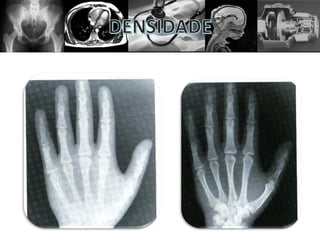

• Densidade óptica é o grau de enegrecimento da

imagem;

• Aponta para a quantidade de radiação interage com a

película radiográfica.

• O mAs altera somente a quantidade ou a produção de

raios X. Ele é o fator primário de densidade e

secundário de contraste.

• Quanto maior o mAs maior o enegrecimento da

imagem